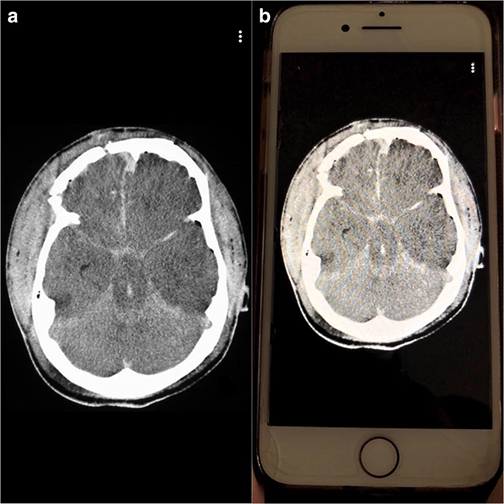

A pilot study conducted by a team of LSU Health New Orleans School of Medicine faculty has found that Snapchat is an effective tool to teach residents emergency radiology. The results are published online in Emergency Radiology available here.

The team compared image analysis and interpretation by radiology residents using Snapchat on smartphones with conventional analysis on a single screen in the resident conference room.

Over a four-week period, LSU Health New Orleans radiology residents, who are all millennials, were shown five emergent radiologic cases using Snapchat and five cases of similar content and duration on a classroom projector. All images depicted diagnoses requiring immediate communication to ordering physicians. Performance was scored 0–2 (0 = complete miss, 1 = major finding, but missed the diagnosis, 2 = correct diagnosis) by two attending radiologists in consensus.

“All residents performed better on Snapchat each week,” says Dr. Spieler, who is also an Associate Professor of Radiology, Internal Medicine, Urology, & Cell Biology and Anatomy at LSU Health New Orleans. “Their accuracy rate was higher using Snapchat than a traditional classroom screen.”

radiology image and on image on smartphone